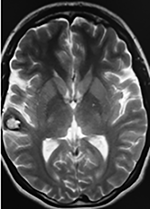

La TAC muestra un área hiperdensa a nivel frontal izquierdo heterogénea que no refuerza con medio de contraste.

LA RMN muestra una lesión bien circunscrita frontal parasagital izquierda con edema perilesional, hiperintensa en T1 y T2, de contenido sólido y quístico, con poca captación del medio de contraste.

Se realizó craneotomía frontal para abordaje interhemisférico anterior.

Se realiza resección total de la lesión de contenido hemático oscuro-verdoso, consistente en un angioma cavernoso. La RMN postoperatoria se observa solo la brecha quirúrgica sin evidencia de lesión.

Figura 4:

Imágenes prequirúrgicas y postquirúrgicas de lesión multiloculada del caso 9.